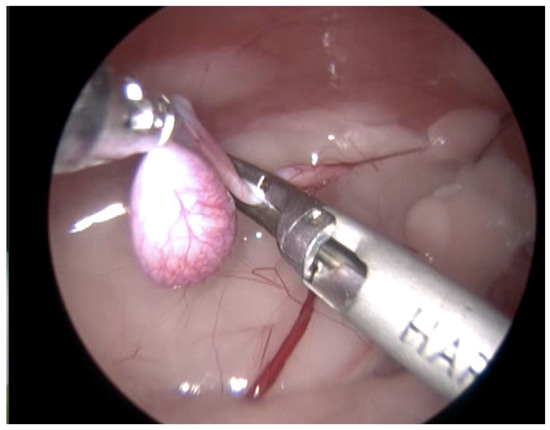

Figure 3.

Technique with two access ports. View of the coagulation and cutting maneuvers of the vascular pedicle, spermatic cord, and gubernaculum, performed with an advanced bipolar energy device.

In 13 cases, the coagulation and cutting of the vascular pedicle, the spermatic cord, and the gubernaculum were performed with advanced electrothermal bipolar energy devices (eight with the Laparoscopic Tissue Sealer G2-ENSEAL® Ethicon-Johnson & Johnson (New York, NY, USA) and five with LigaSureTM Covidien-Medtronic (Dublin, Ireland), https://www.jnjmedtech.com/global, https://www.medtronic.com/covidien/en-us/index.html accessed on 27 October 2022) (Figure 3). In five cases, this procedure was made with a Harmonic scalpel device (Figure 4 and Supplementary Video S1) (Harmonic ACE® +Shears and Gen11 generator Ethicon-Johnson & Johnson), and in one case, with the use of a monopolar energy hook.